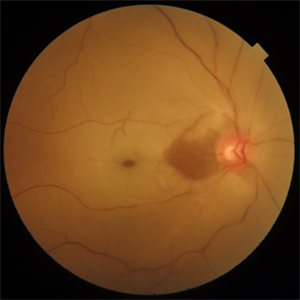

Cilioretinal Artery Sparing CRAO

Cilio retinal artery sparing CRAO in a 40-year-old gentleman post surgery for varicose veins.